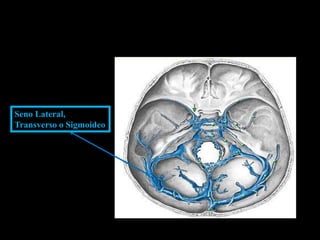

Seno Lateral,

Transverso o Sigmoideo